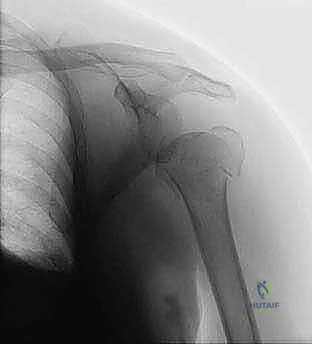

- الأشعة السينية (X-rays): يتم أخذ صور من زوايا متعددة (أمامية خلفية، جانبية، وإبطية) لتحديد نوع الكسر وموقعه.

- التصوير المقطعي المحوسب (CT Scan): في الكسور المعقدة (ثلاثية أو رباعية الأجزاء)، يُعد التصوير المقطعي ثلاثي الأبعاد ضرورياً جداً. فهو يمنح الجراح خريطة دقيقة لحجم الشظايا العظمية ومواقعها، مما يساعد في التخطيط الجراحي الدقيق قبل دخول غرفة العمليات.

يتم استخدام جهاز الأشعة المرئية (Fluoroscopy) طوال فترة العملية لضمان الرؤية الدقيقة للكسر ومسار الأسلاك دون الحاجة لفتح الجلد.